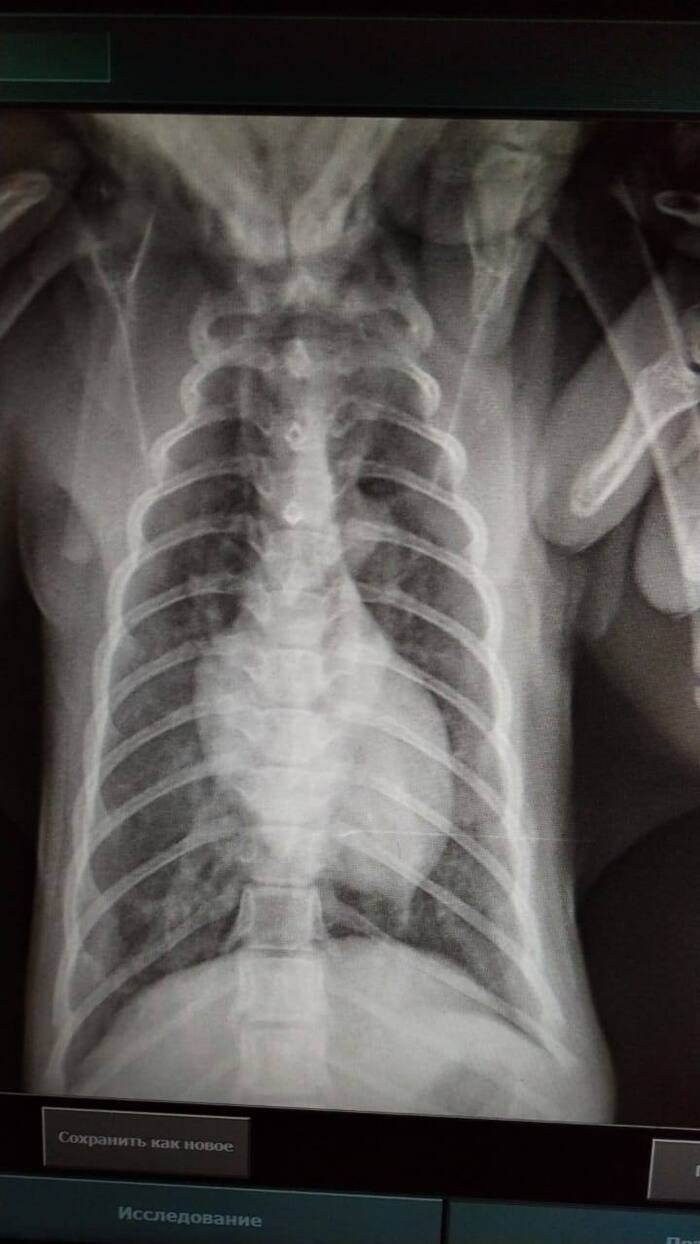

Всем привет. Хозяин (слава летающему чайнику) вышел на звяь и отнес котенка в Леноблвет на анализы. Он, кстати, взял его на Юле от домашней кошки. Денег нет, платим мы. Котенок живой. Температуру держит, активнее, чем вчера. Как придет кровь, будет ясно, какие инфузии можно будет делать.